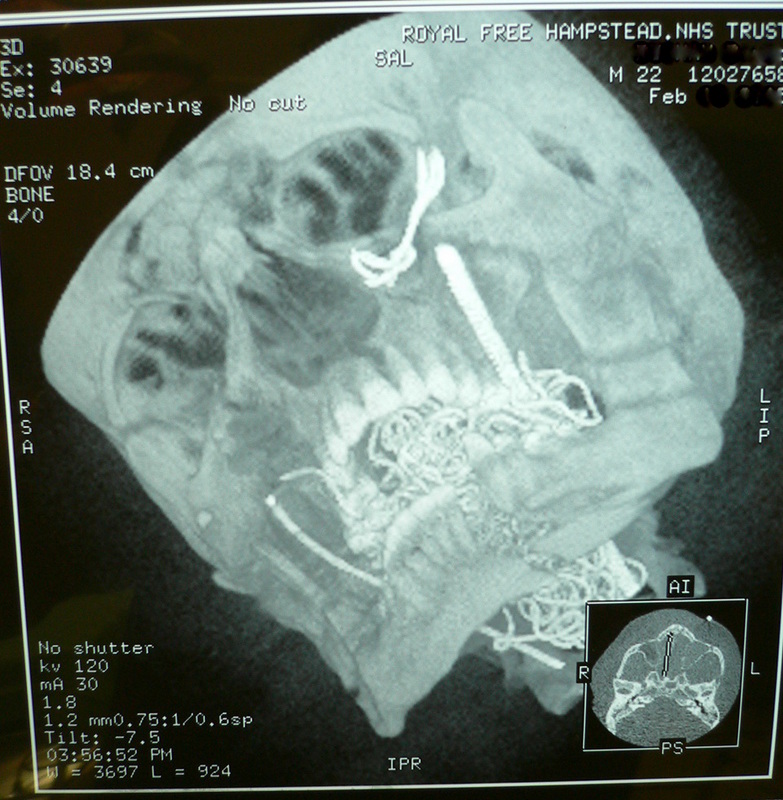

CT Scan Of Fractured Cheekbone And Orbit